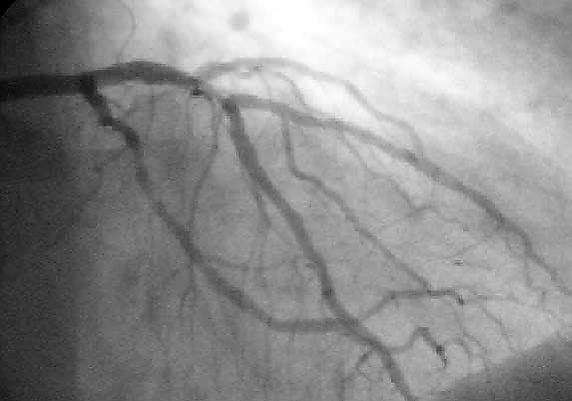

Коронарография

Коронарография — рентгеноконтрастный метод исследования, который является наиболее точным и достоверным способом диагностики ишемической болезни сердца (ИБС), позволяя точно определить характер, место и степень сужения коронарной артерии.

Этот метод является «золотым стандартом» в диагностике ИБС и позволяет решить вопрос о выборе и объёме проведения в дальнейшем таких лечебных процедур, как баллонная ангиопластика (ангиопластика), стентирование и коронарное шунтирование.

Во время коронарографии интервенционный кардиолог вводит водорастворимое рентгеноконтрастное вещество последовательно в левую и правую коронарные артерии, используя для этого ангиографические катетеры. При каждом таком введении рентгеноконтрастное вещество быстро заполняет просвет артерии на всем её протяжении. В потоке рентгеновских лучей туго контрастированная артерия отбрасывает тени на детектор ангиографа, отображая информацию о своем внутреннем рельефе. Так, выполнив съёмку в нескольких проекциях, можно получить наиболее полное представление об анатомии и степени поражения русла коронарных артерий. Стоит отметить, что во время исследования пациент находится в потоке ионизирующего излучения, и эквивалентная доза облучения может составить, в среднем, 2-10 миллизиверт за одно исследование.